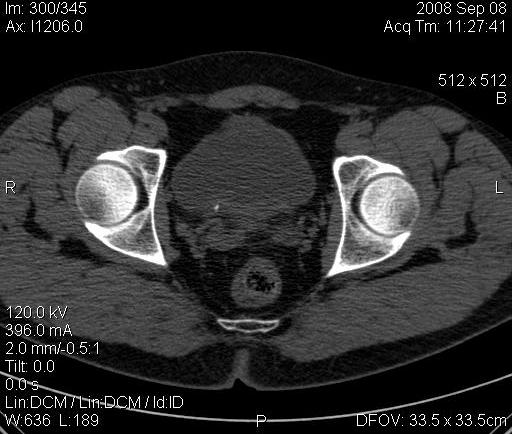

Re: КТ Почек. Почечная колика

Почечная колика; на последнем аксиальном скане чётко виден мелкий (2 мм) камень в устье правого мочеточника.

Dr.Mario писал(а):Почечная колика; на последнем аксиальном скане чётко виден мелкий (2 мм) камень в устье правого мочеточника.

Для невладеющего КТ,очень четка видна аномалия на 3-4х снимках.А вот на 4-м скане в проксим.сегменте цистоида тоже есть гиперденсное точечное образование-не камень случайно?